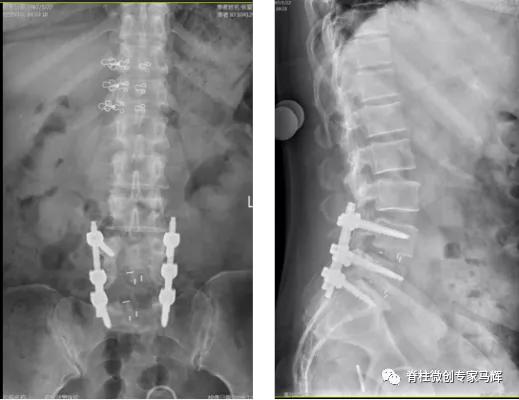

2018年腰椎术前

2018年腰椎术后

2019年腰椎内固定取出后